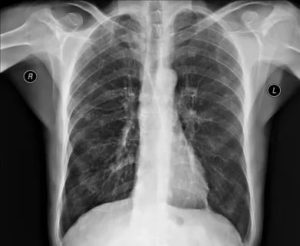

Эмфизема легких у мужчины 50 лет. На обзорной рентгенограмме грудная клетка имеет колоколообразную форму, диафрагма уплощена, уровень стояния ее низкий, сосудистый рисунок легких обеднен. Незначительная изогнутость отдельных сосудов. Тень сердца уменьшена, легочный ствол выбухает.